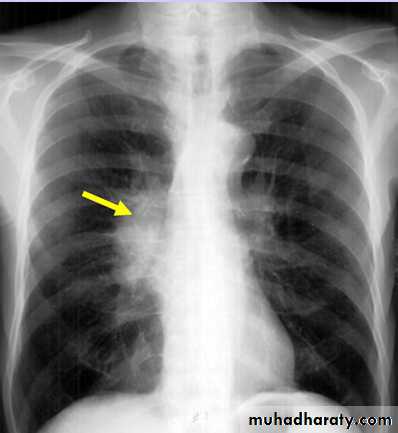

Unilateral rt. Hilar LNE, increase density, lobulated outline.

Lymph node enlargement: Usually more than one hilar node is enlarged, so in patients with lymphadenopathy the hilum appears lobulated in outline.

Unilateral enlargement of hilar lymph nodes may be due to the following:

1- Metastases from carcinoma of the bronchus in which case the primary tumour is often visible.

metastases from other primary sites are rare.

2- Malignant lymphoma.

3- Infections, particularly tuberculosis, and histoplasmosis

in endemic areas. Tuberculosis is the commonest cause of unilateral hilar adenopathy in children.